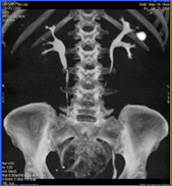

Endo-Urología y Litiasis E Artozki, L Labairu, I Linazasoro. |

Endo-Urología y Litiasis JA López García, E Artozki, L Labairu, I Linazasoro. |